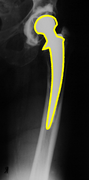

b. Medical application: Hip prosthesis registration

Hip replacement is a surgical procedure in which the hip joint is replaced by a prosthetic implant. Such joint replacement surgery generally is conducted to relieve arthritis pain or fix severe physical joint damage. In the short term post-operatively, infection is a major concern. Deep infection will often require one or two stage revision surgery. Recurrent dislocation is another indication for revision. In the long term, many problems relate to osteolysis from wear debris. An inflammatory process causes bone resorption and subsequent loosening or fracture often requiring revision surgery.

The following figure shows a result of our method. The red channel of the first image represents the template. By applying the inverse of the recovered transformation to the observation, we get a registered image shown in the green channel. The contour overlay image shows the contour of the registered observation object in yellow color over the template image.

| Registration of hip prosthesis X-ray images. Each image pair has been taken over a period of time about the same patient. The overlayed contour in the second row shows the aligned contour of the corresponding image in the first row. For each pair, we have also evaluated the measure. | ||||